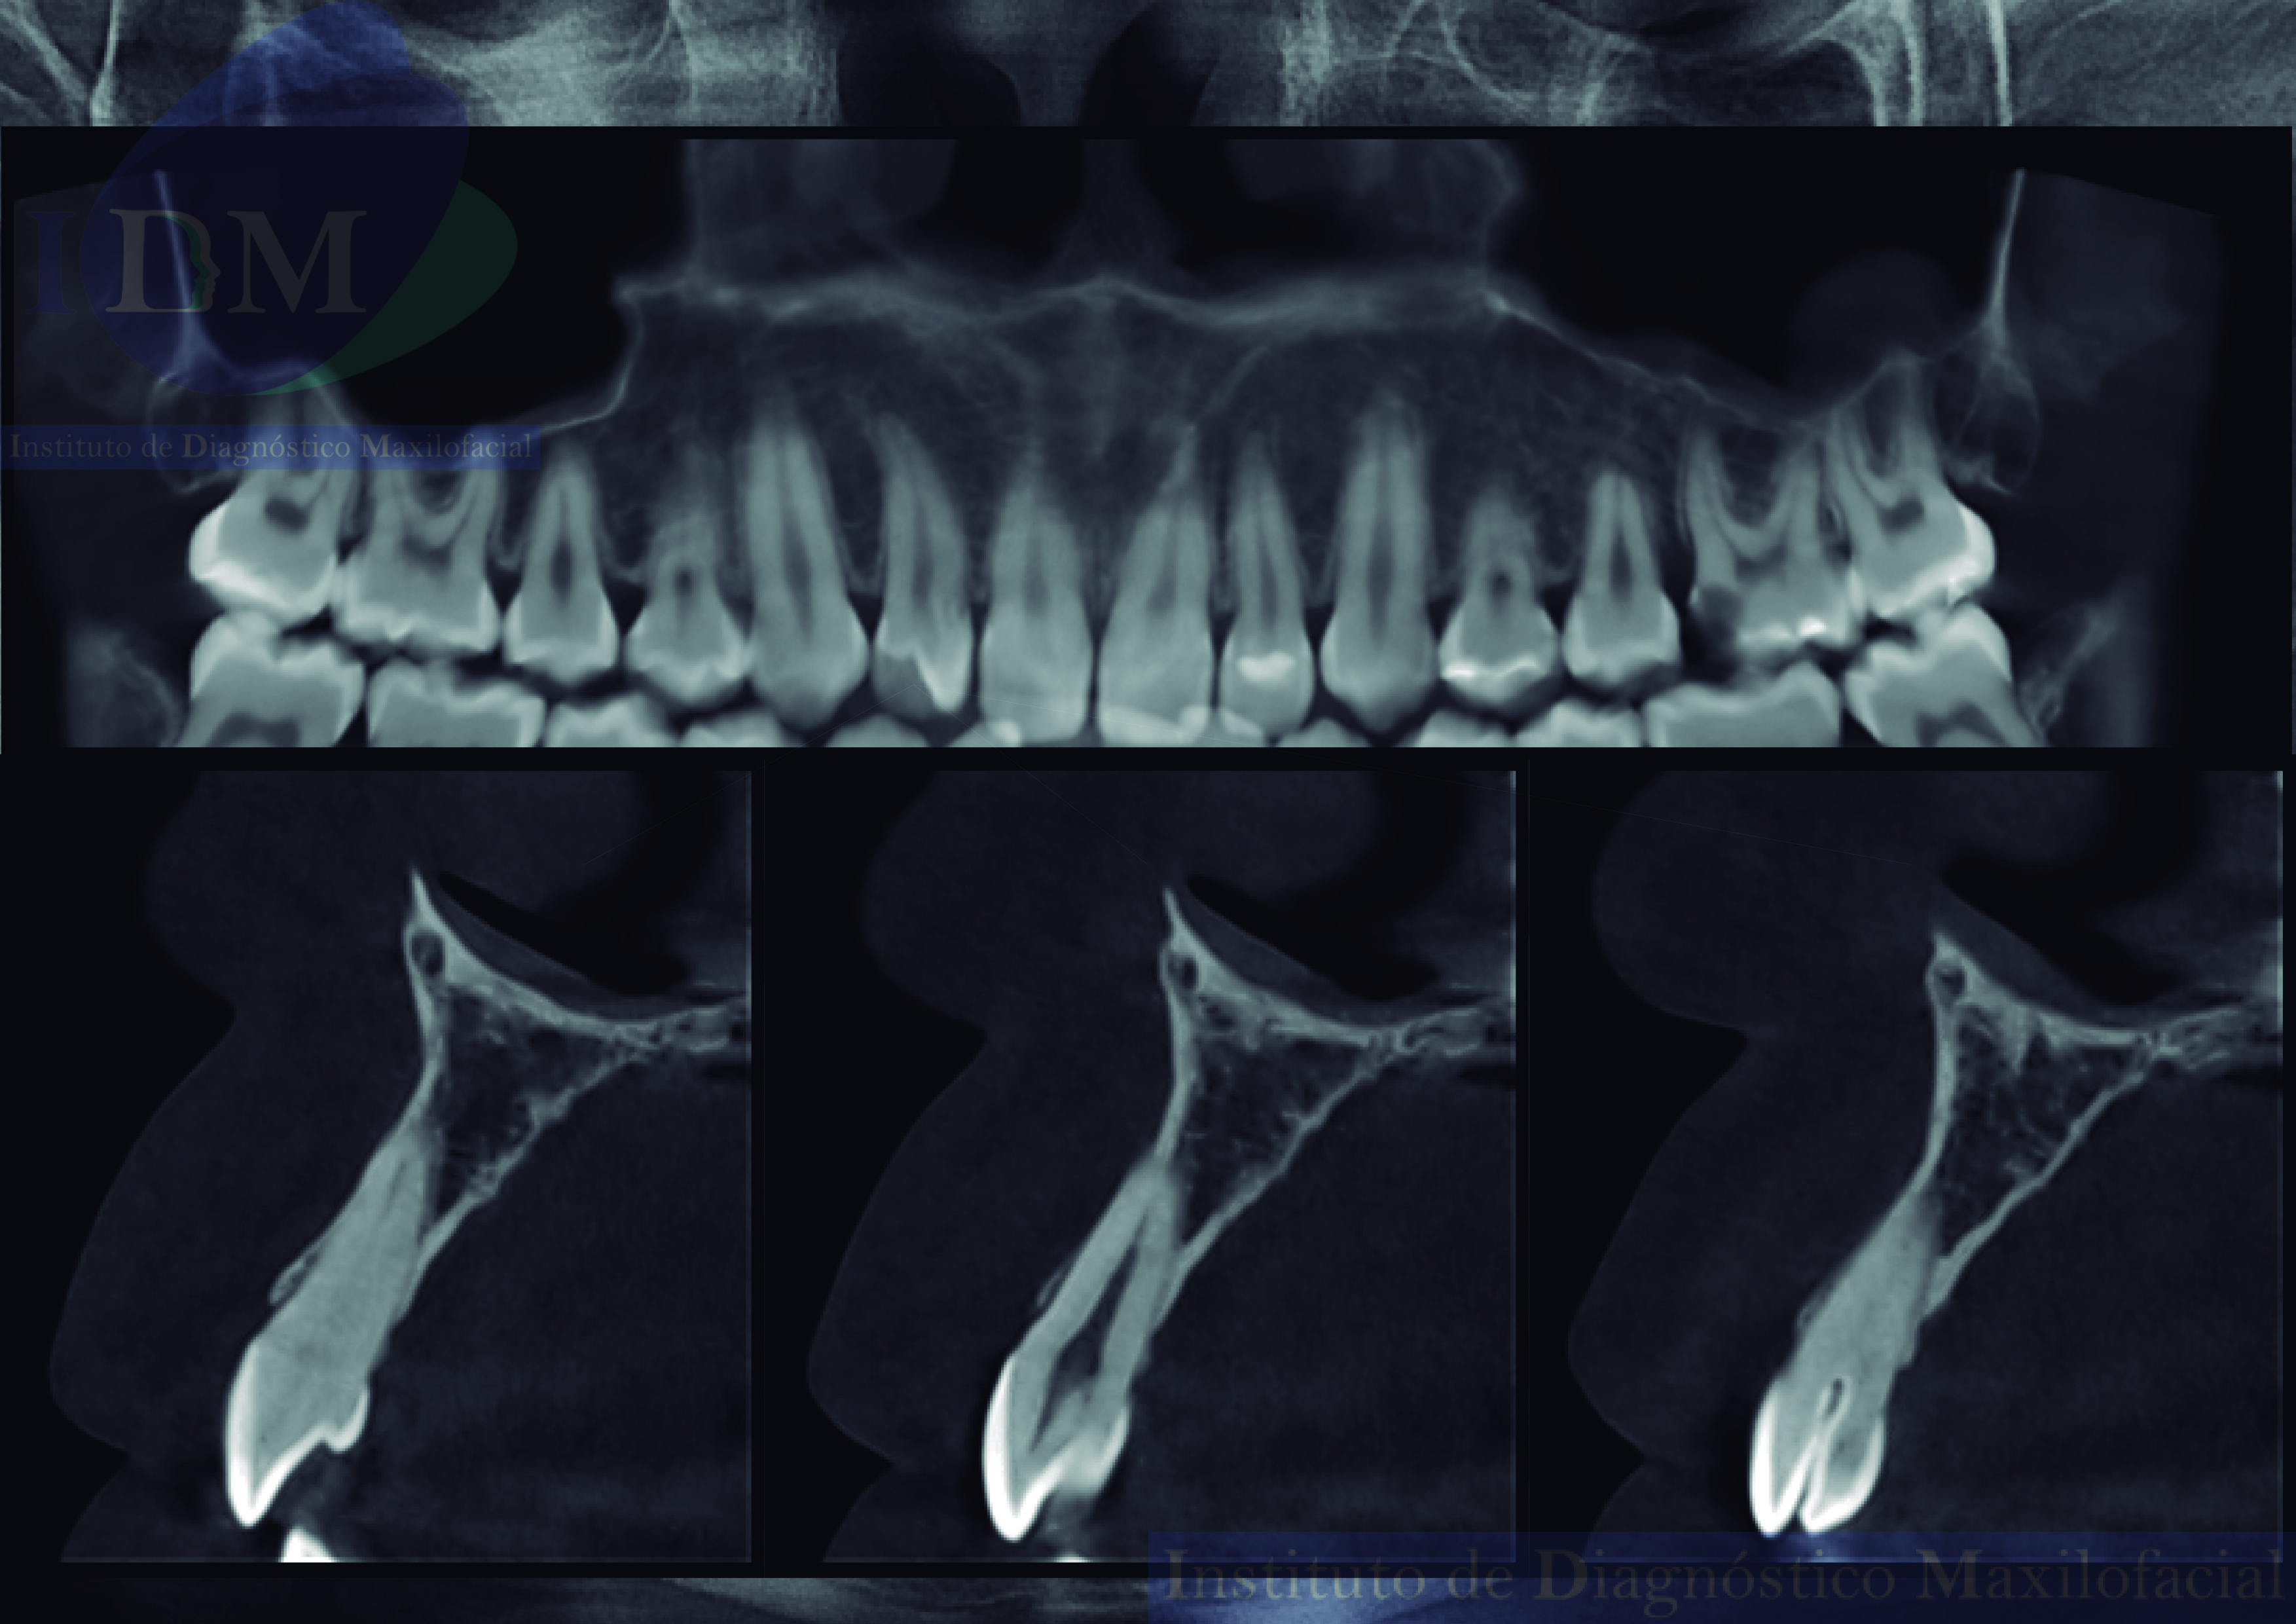

A la evaluación de la tomografía volumétrica (CBCT) en los cortes axiales (Figura 2) y transaxiales (Figura 3), se aprecia bifurcación del conducto que se extiende hasta tercio cervical radicular de pieza 1.2.

CORTES AXIALES

CORTES TRANSAXIALES